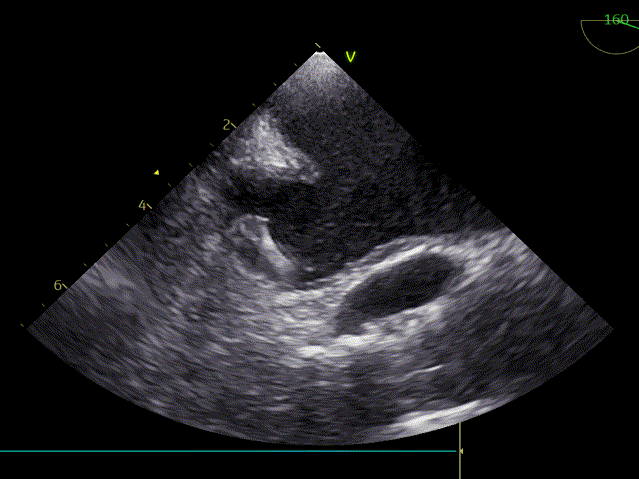

术前超声心动图:

主动脉瓣狭窄(重度,跨瓣平均压差69mmHg),房颤、心衰,反复住院2年;瓣环直径2.4cm,AV 5.0m/s EF 59%。

TEE45度检查左心耳